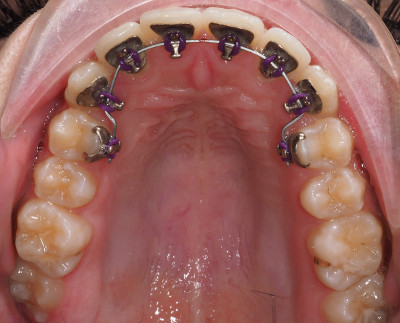

L’ortodonzia linguale offre i più alti risultati funzionali ed estetici, per ogni tipo di trattamento, per ogni paziente.

Il giorno in cui viene applicato il vostro apparecchio tutto viene controllato, cercando di rendere il vostro trattamento il più confortevole possibile.

L’apparecchio non si vede ma i risultati si! Giorno dopo giorno potrete apprezzare il proseguire della terapia.

L’apparecchio su misura

L’apparecchiatura è costruita con le più moderne tecnologie.

Si parte dalla scansione 3d delle tue arcate, da qui vengono realizzati dei modelli virtuali su cui viene impostato il trattamento ottimale già concordato con il tuo specialista in ortodonzia.

In seguito vengono costruiti, per ogni elemento dentale, degli attacchi completamente personalizzati in modo da offrire il massimo confort.

Tutti gli archi necessari alla tua terapia sono poi realizzati su misura e confezionati da un robot in base a sequenze efficaci.